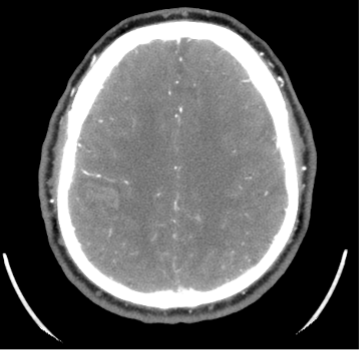

Caso 35

Angio TC